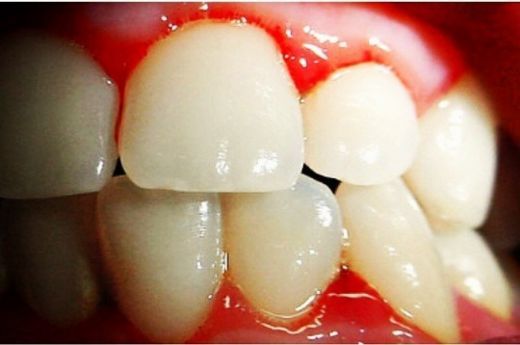

Eğer yaşadığınız kanama yalnızca lekelenme şeklindeyse, bu bazı kadınlar için gebelik döneminde sıkça karşılaşılan bir durumdur. Ancak, eğer kanama yoğun ve sürekli ise, bu durum daha fazla değerlendirilmesi gereken bir durumu işaret edebilir.

Rahim veya Vajina Sorunları

Kanama durumu, rahim veya vajinada bir sorun olabileceği anlamına gelebilir. Ancak bu, mutlaka böyle olduğu anlamına gelmez. Kesin bir değerlendirme için doktora başvurmanız en doğrusu olacaktır.